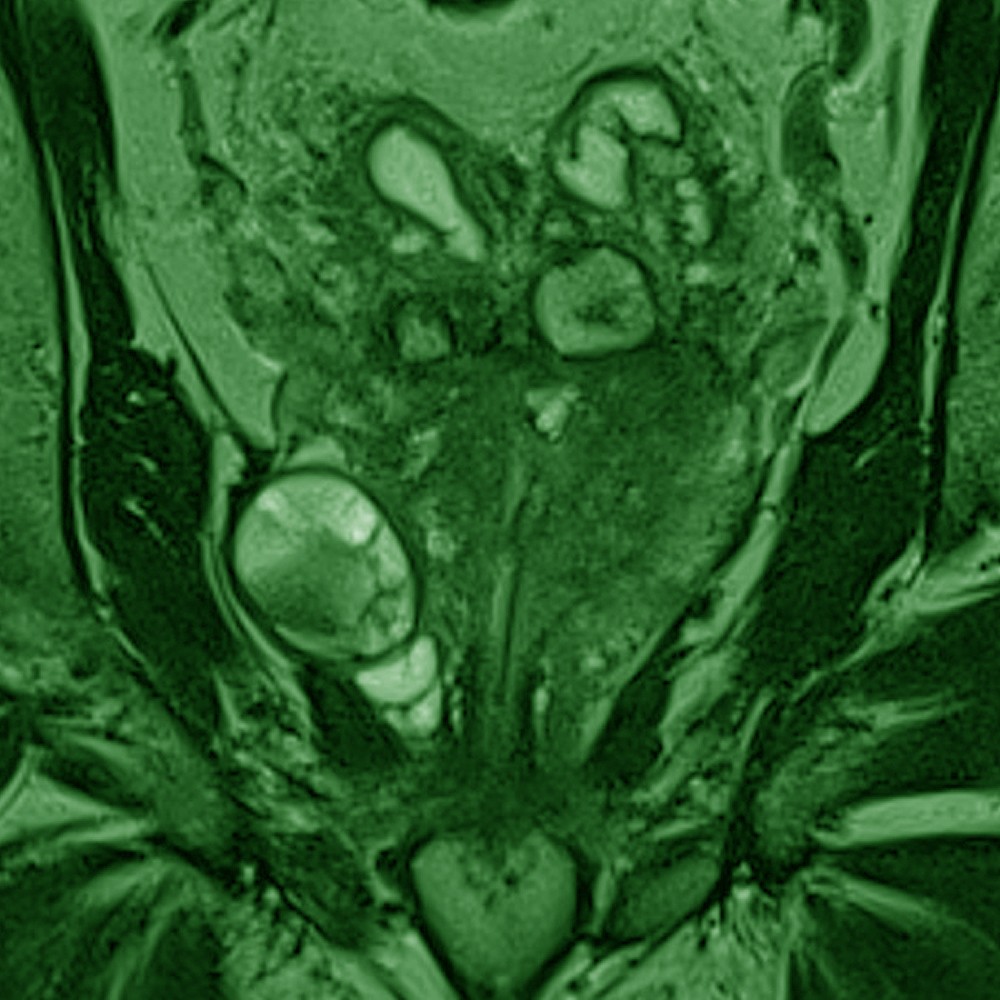

Willkommen zum 16. Petersberger Symposium – dem zentralen Treffpunkt für Expertinnen und Experten der klinischen Radiologie. Unter dem Motto „Radiologie meets Urologie“ widmen wir uns 2026 der Zukunft des Prostata-Screenings: von technischer Innovation über künstliche Intelligenz bis hin zu neuen diagnostischen und therapeutischen Standards.

Zukunft des Prostata-Screenings

• Innovative Bildgebung und Screeningstrategien

• Fortschritte in der MRT-basierten Diagnostik